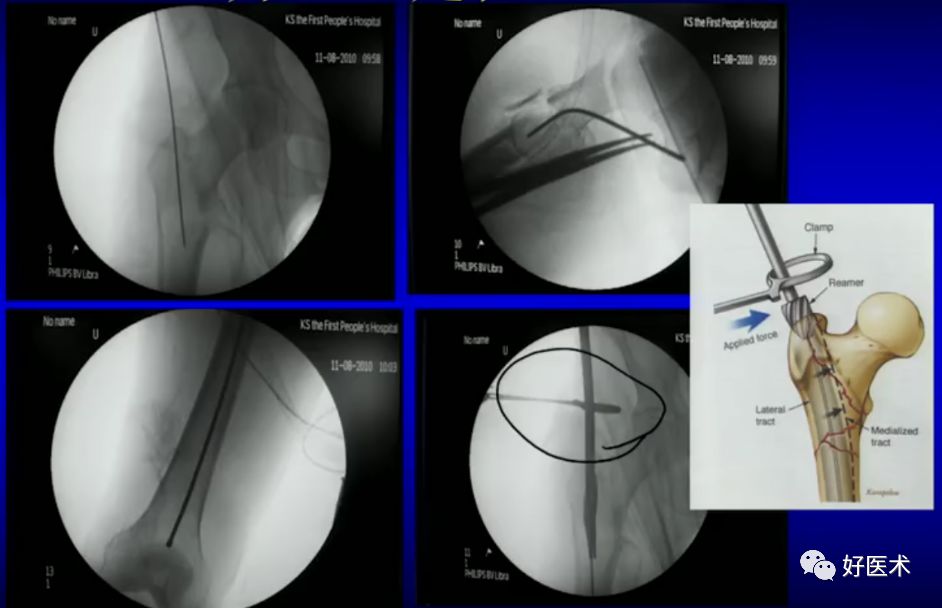

1.撬拨技术

用克氏针或斯氏针对移位的骨折块进行撬拨复位。

体表定位与撬棒置顶

撬棒置顶后内收情况

正位进针位置调整情况

主钉插入后的导针正侧位

2.顶棒技术

用钉棒顶压移位骨折块来帮助复位。

3.钳夹技术

用复位钳、毛巾钳或骨盆复位钳钳夹移位骨块帮助复位。